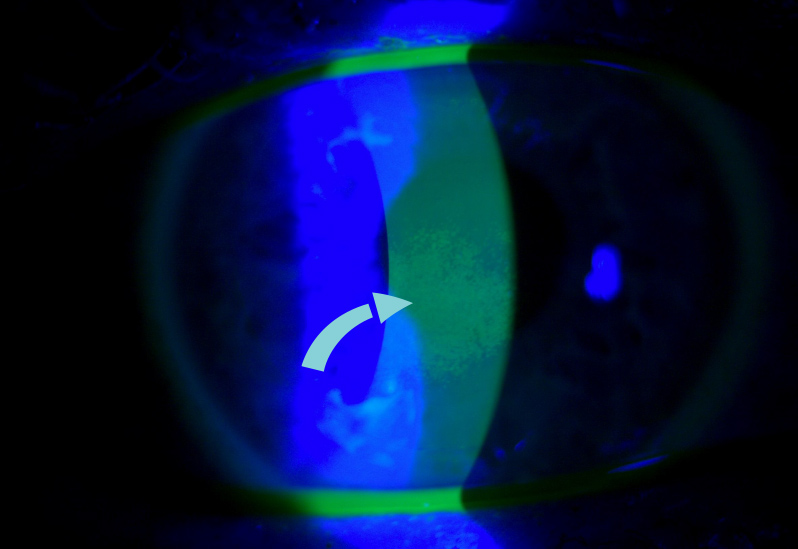

- Slit Lamp Exam